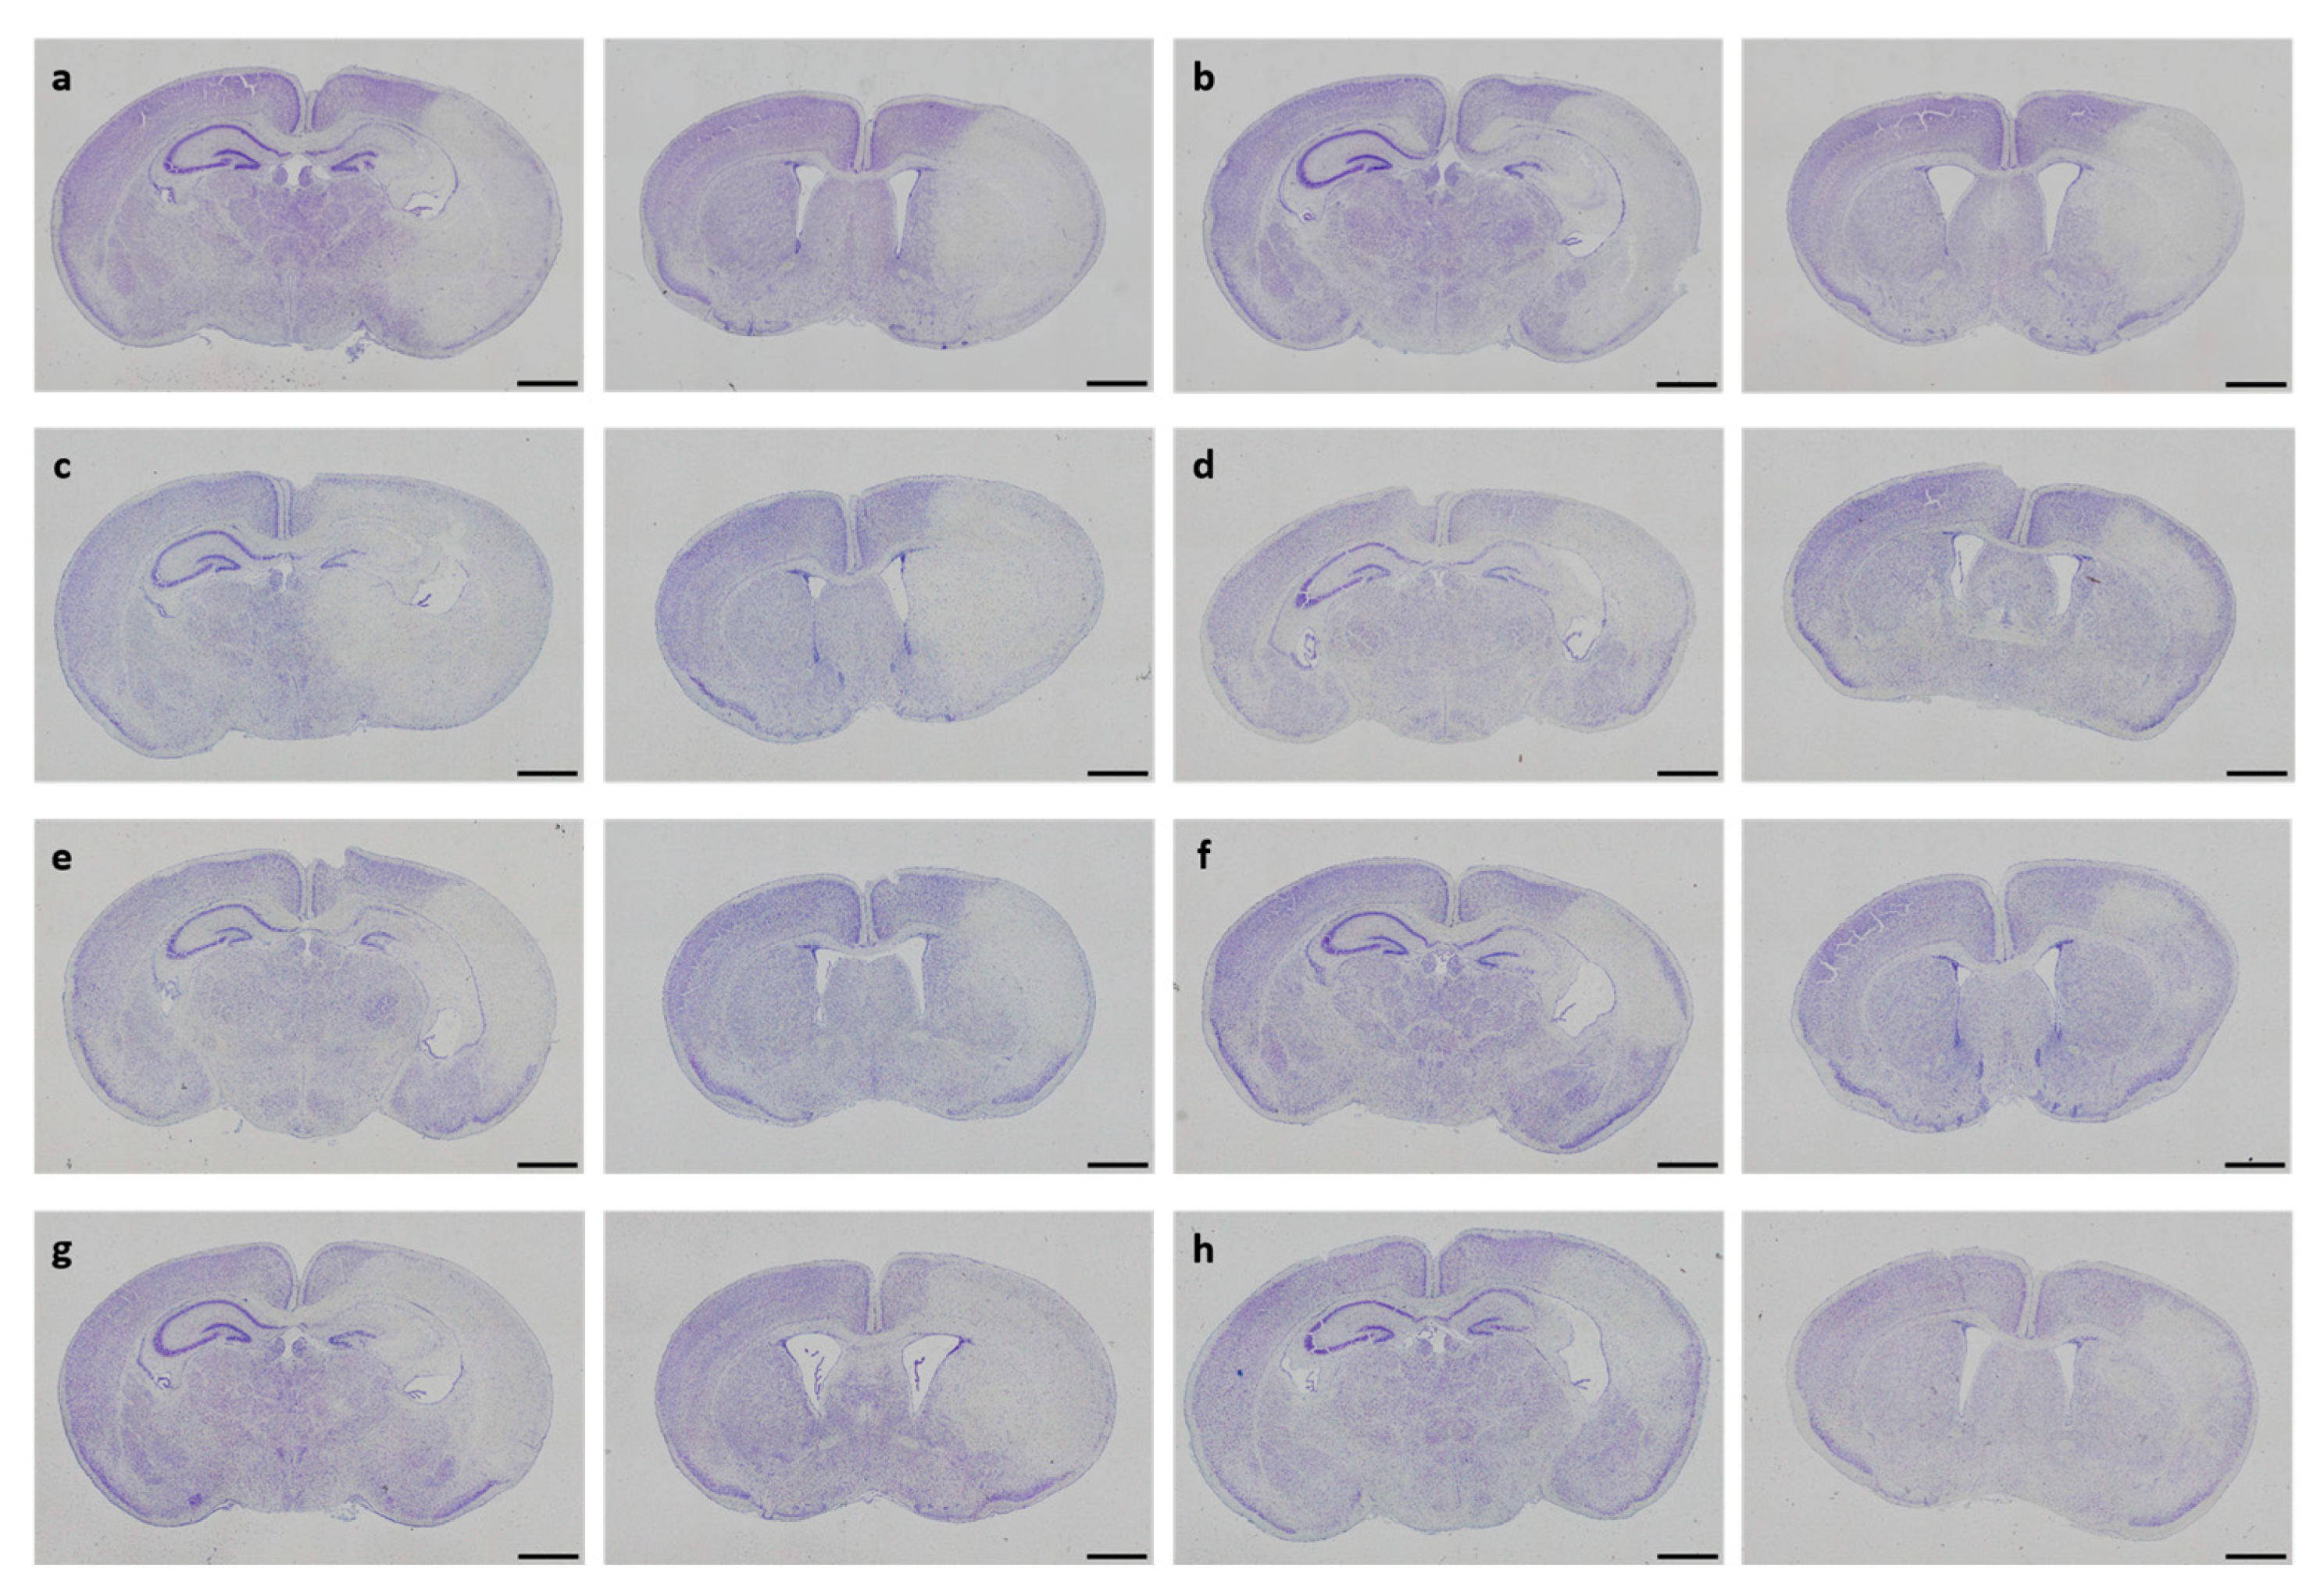

3.2. Neuropathological Injury

| Treatment Group | Number of Animals, n | Total Injury Score, Median (25th; 75th Percentile) | p-Value |

|---|---|---|---|

| Control | 16 | 3.5 (1.0; 10.5) | |

| Solvent control | 16 | 8.3 (0.9; 12.0) | |

| DHEA 0.1 µg/g bw | 15 | 5.0 (0.5; 13.0) | |

| DHEA 1 µg/g bw | 17 | 9.5 (1.5; 12.0) | |

| DHEA 10 µg/g bw | 16 | 5.0 (1.1; 7.9) | |

| DHEAS 0.1 µg/g bw | 16 | 7.5 (1.3; 12.8) | |

| DHEAS 1 µg/g bw | 17 | 4.0 (1.3; 11.0) | |

| DHEAS 10 µg/g bw | 17 | 6.5 (1.5; 12.5) | 0.829 1 |